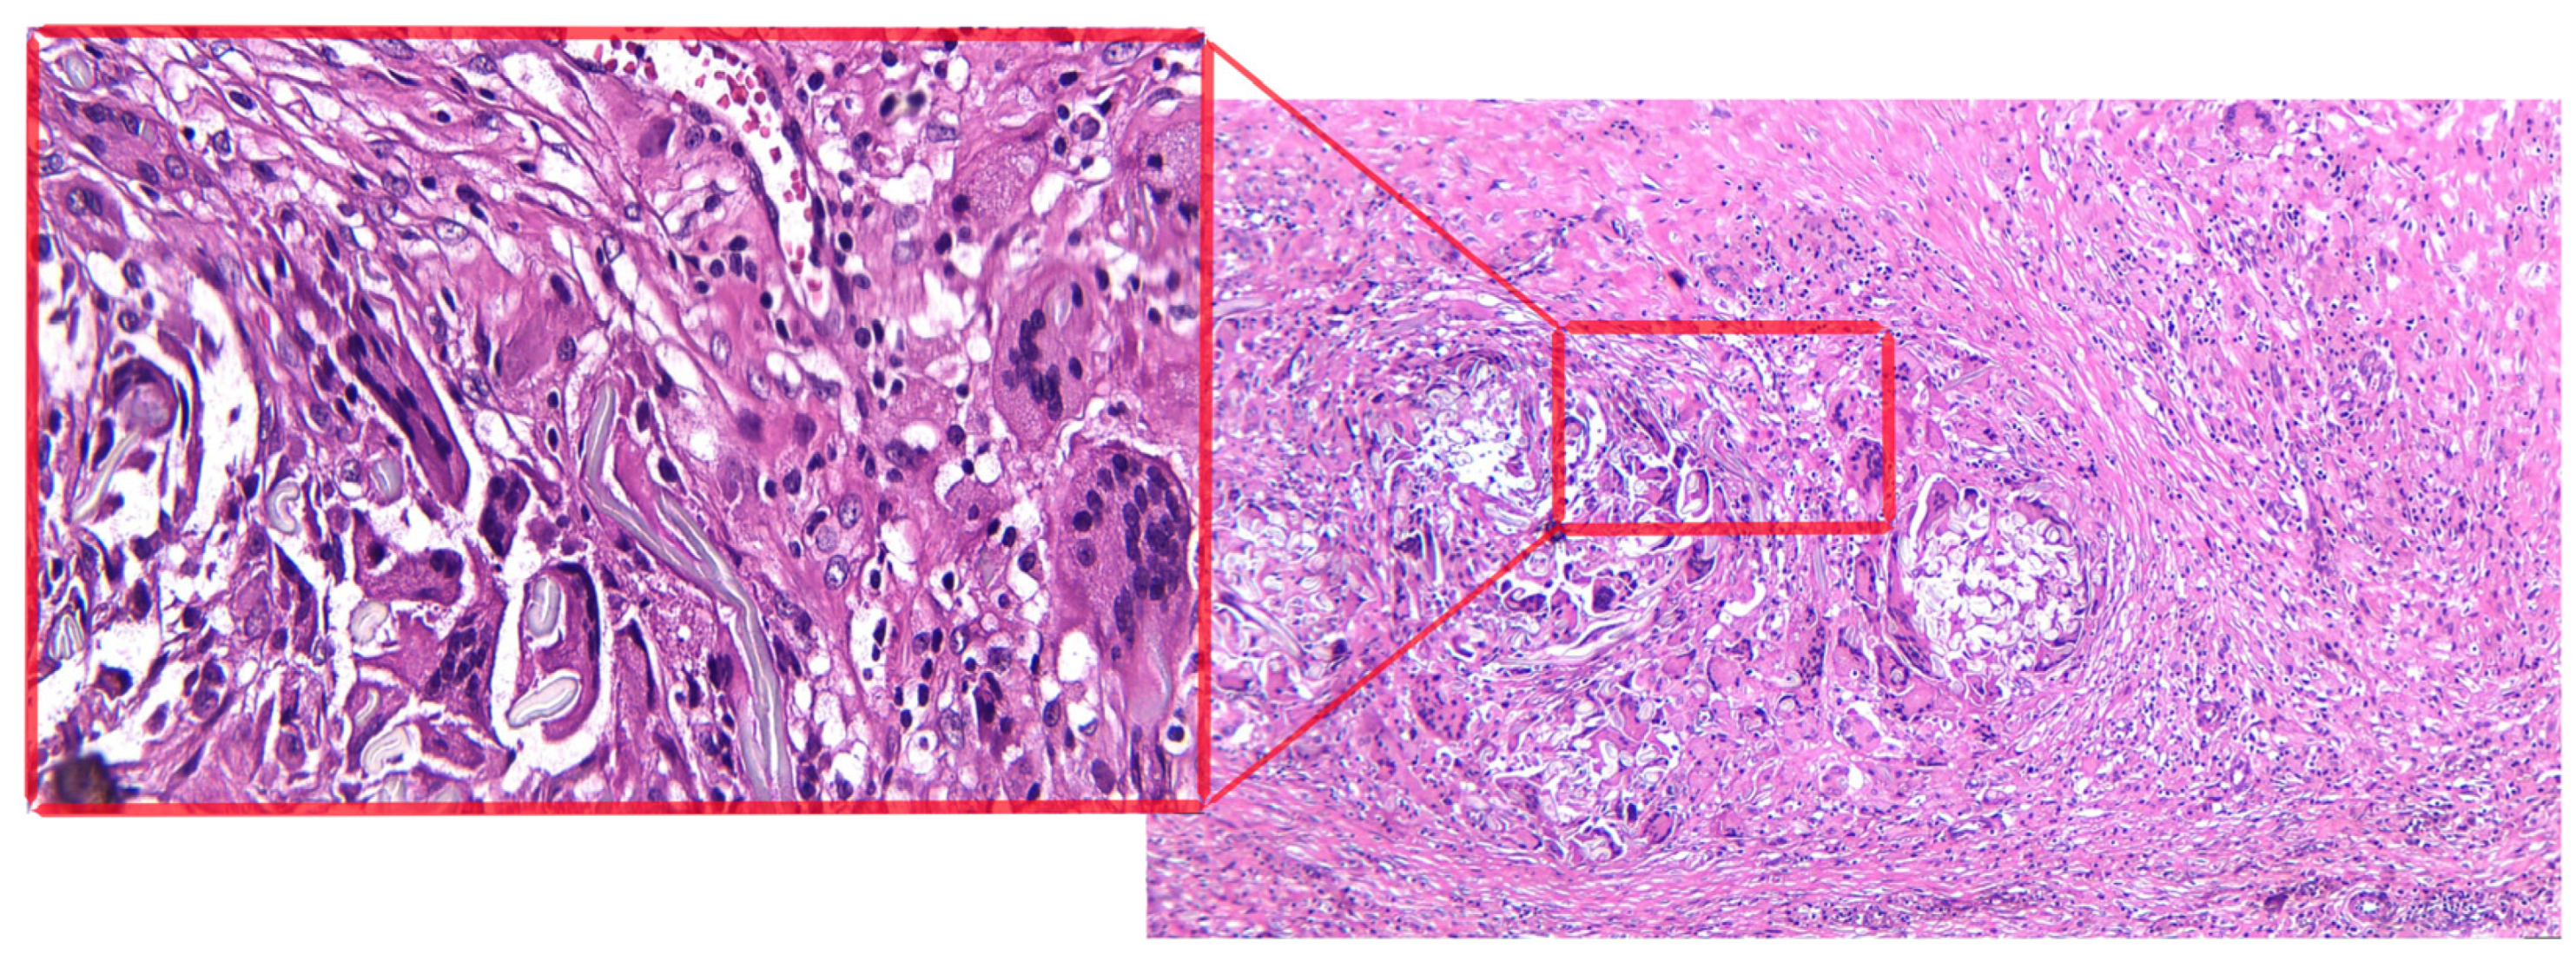

- Left adnexal tumor mass: tissue fragment with a histopathological aspect of conjunctive-adipose and vascular–nervous tissue presenting multiple foci of chronic granulomatous inflammation with multinucleated foreign body giant cells arranged around exogenous, acellular, translucent materials; diffuse areas of fibroblast–fibrocystic proliferation; numerous groups of foamy histiocytes, some with a multinucleolate appearance; and marked capillary hyperemia, interstitial edema, and diffuse regions of hematic extravasation. The ovarian histological structure is identified at a certain level, with multiple foci of chronic granulomatous inflammation with foreign body multinucleated giant cells, in addition to tubal wall with lesions of chronic xanthogranulomatous salpingitis, discrete tubular epithelial hyperplasia, moderate capillary hyperemia, and intramural interstitial edema;

- Right subhepatic tumor mass: tissue fragment with a histopathological aspect of conjunctive-adipose and vascular–nervous tissue presenting multiple foci of chronic granulomatous inflammation with multinucleated foreign body giant cells arranged around exogenous, acellular, translucent materials; diffuse areas of fibroblast–fibrocystic proliferation; numerous groups of foamy histiocytes, some with a multinucleolate appearance; and moderate capillary hyperemia, interstitial edema (Figure 3).